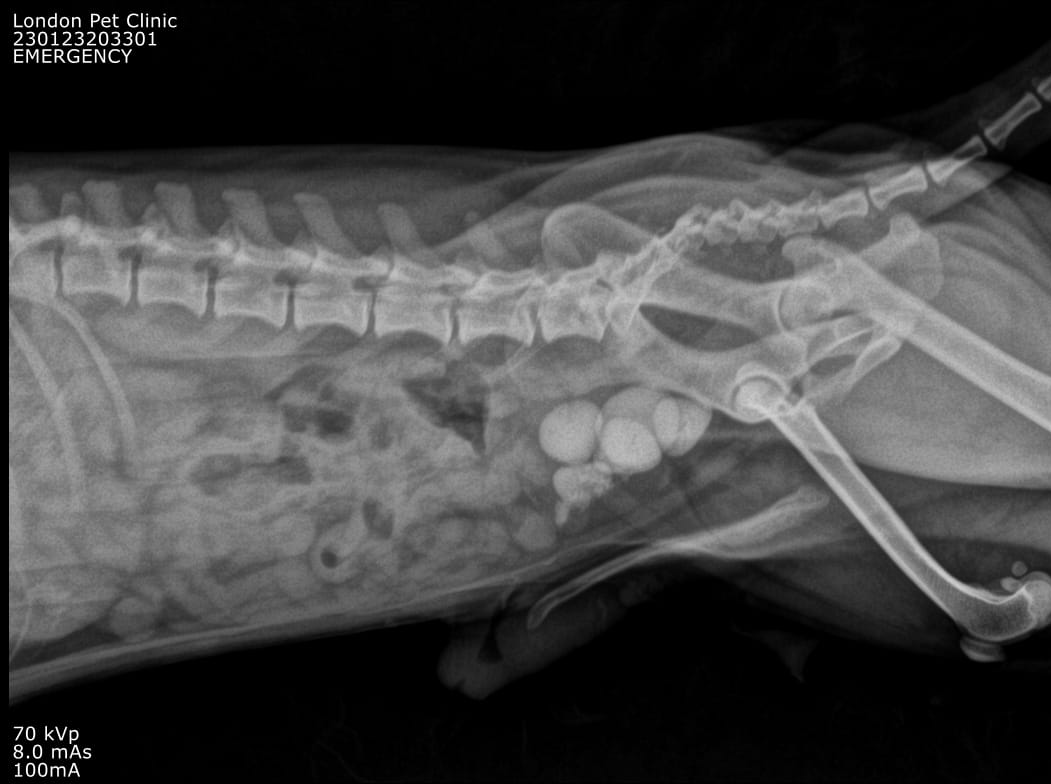

Abdominal Radiographs: Multiple radiopaque uroliths visible in the bladder

Multiple radiopaque uroliths visible in the bladder